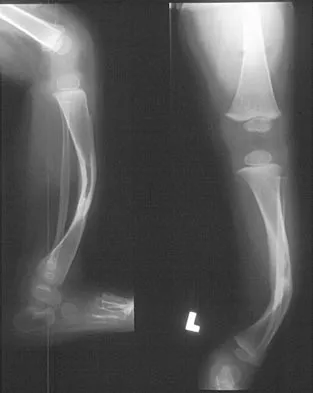

Figures 14a and 14b show the initial radiographs of an 18-year-old man who fell while snowboarding. Figures 14c and 14d show the radiographs obtained following closed reduction. Examination reveals that the elbow is stable with range of motion. Management should now consist of

The initial radiographs reveal a simple elbow dislocation without associated fractures. After successful closed reduction, the range of stability should be assessed. If the elbow is stable, nonsurgical management should consist of a short period of immobilization followed by range-of-motion exercises. Immobilization for more than 3 weeks results in significant elbow stiffness. Surgical repair is indicated for dislocations that are irreducible, have associated fractures, or where stability cannot be maintained with closed treatment. Cohen MS, Hastings H II: Acute elbow dislocations: Evaluation and management. J Am Acad Orthop Surg 1998;6:15-23.